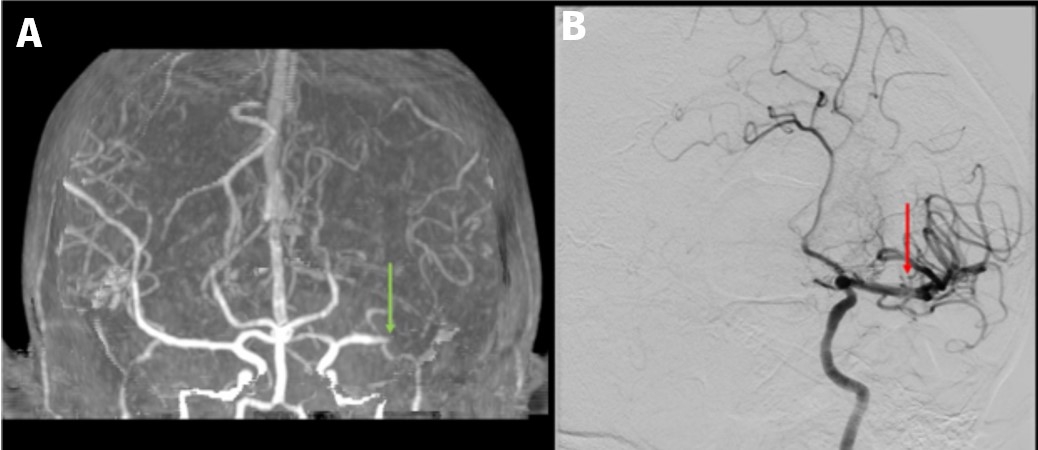

Investigations: CT angiography and CT perfusion revealed reduced opacification in the left MCA bifurcation and a left M2 thrombus (Figure 1A). The contrast echocardiogram showed a normal-sized left ventricle with severely reduced ejection fraction (25%, down from 30% six months prior), diffuse hypokinesis, grade III diastolic dysfunction, and a left ventricular thrombus, with no patent foramen ovale.

Treatment: Given the high suspicion for cardioembolic stroke, the patient received intravenous tenecteplase within the 3-hour window. Mechanical thrombectomy was planned but aborted due to spontaneous recanalization. Post-thrombolytic angiography confirmed reperfusion of the left MCA with residual distal M3 thrombus (Figure 1B).MRI confirmed infarcts in the left MCA distribution and right precentral gyrus, with no evidence of hemorrhagic transformation. Anticoagulation was initiated for secondary prevention. Statins were withheld due to concerns about mitochondrial toxicity.